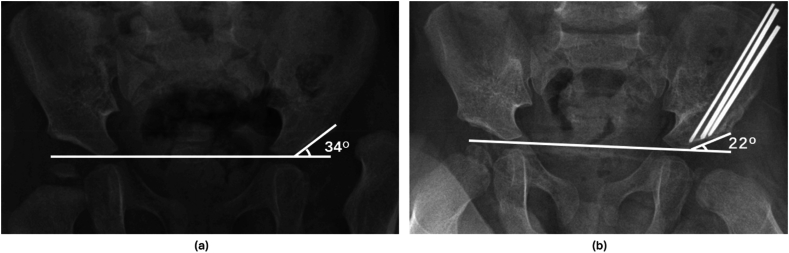

Methods: A retrospective review was performed of all Salter osteotomies performed at a single tertiary care children's hospital from 2009 to 2024. Demographic and clinical variables were extracted from electronic medical records. Acetabular indices (AIs) on preoperative and 3-month postoperative AP pelvic radiographs were compared to assess the degree of acetabular correction. Traditional and graftless procedures were propensity score matched 1:2 based on age, gender, and preoperative AI. Acetabular correction was compared between the two cohorts using the Wilcoxon Mann-Whitney test.

Results: Forty-seven hips were identified (14 traditional, 33 graftless). Seventy-two percent of patients were female; the mean age at surgery was 29.9 months (range: 15-70). Thirty-eight hips (81%) underwent concomitant open reduction. Propensity score matched analysis demonstrated no significant difference in the degree of acetabular correction between the cohorts (traditional vs graftless: 11.9° ± 5.4 vs 12.7° ± 5.7, P = .69). All osteotomies healed by 3 months, and there were no cases of lost fixation with either technique.